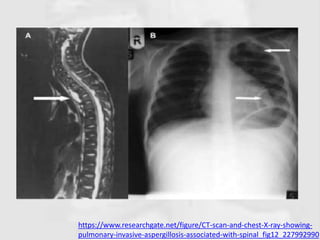

FUNGAL INFECTION

INTRODUCTION

• These are opportunistic infections occurring in an

immuno-compromised host however, may also

affect a normal host

• Air-borne fungi that initially affect the lungs

– Ex: Aspergillosis and Cryptococcus

– Spine is involved by haematogenous spread.

• In children with chronic granulomatous disease,

– Thoracic spine involvement is due to contiguous

spread from the lungs.

CLINICAL PRESENTATION, CLINICAL

FINDINGS AND RADIOGRAPHIC FEATURES

• May mimic those of TB.

• The chest x-ray may show

– A fungal ball or pneumonia.

• The diagnosis by

– Sputum examination and bronchoscopy.

• The immuno-diffusion test is specific for

Aspergillosis and the latex agglutination test for

Cryptococcus.

• A biopsy is performed to confirm the diagnosis.

https://www.researchgate.net/figure/CT-scan-and-chest-X-ray-showing-

pulmonary-invasive-aspergillosis-associated-with-spinal_fig12_227992990